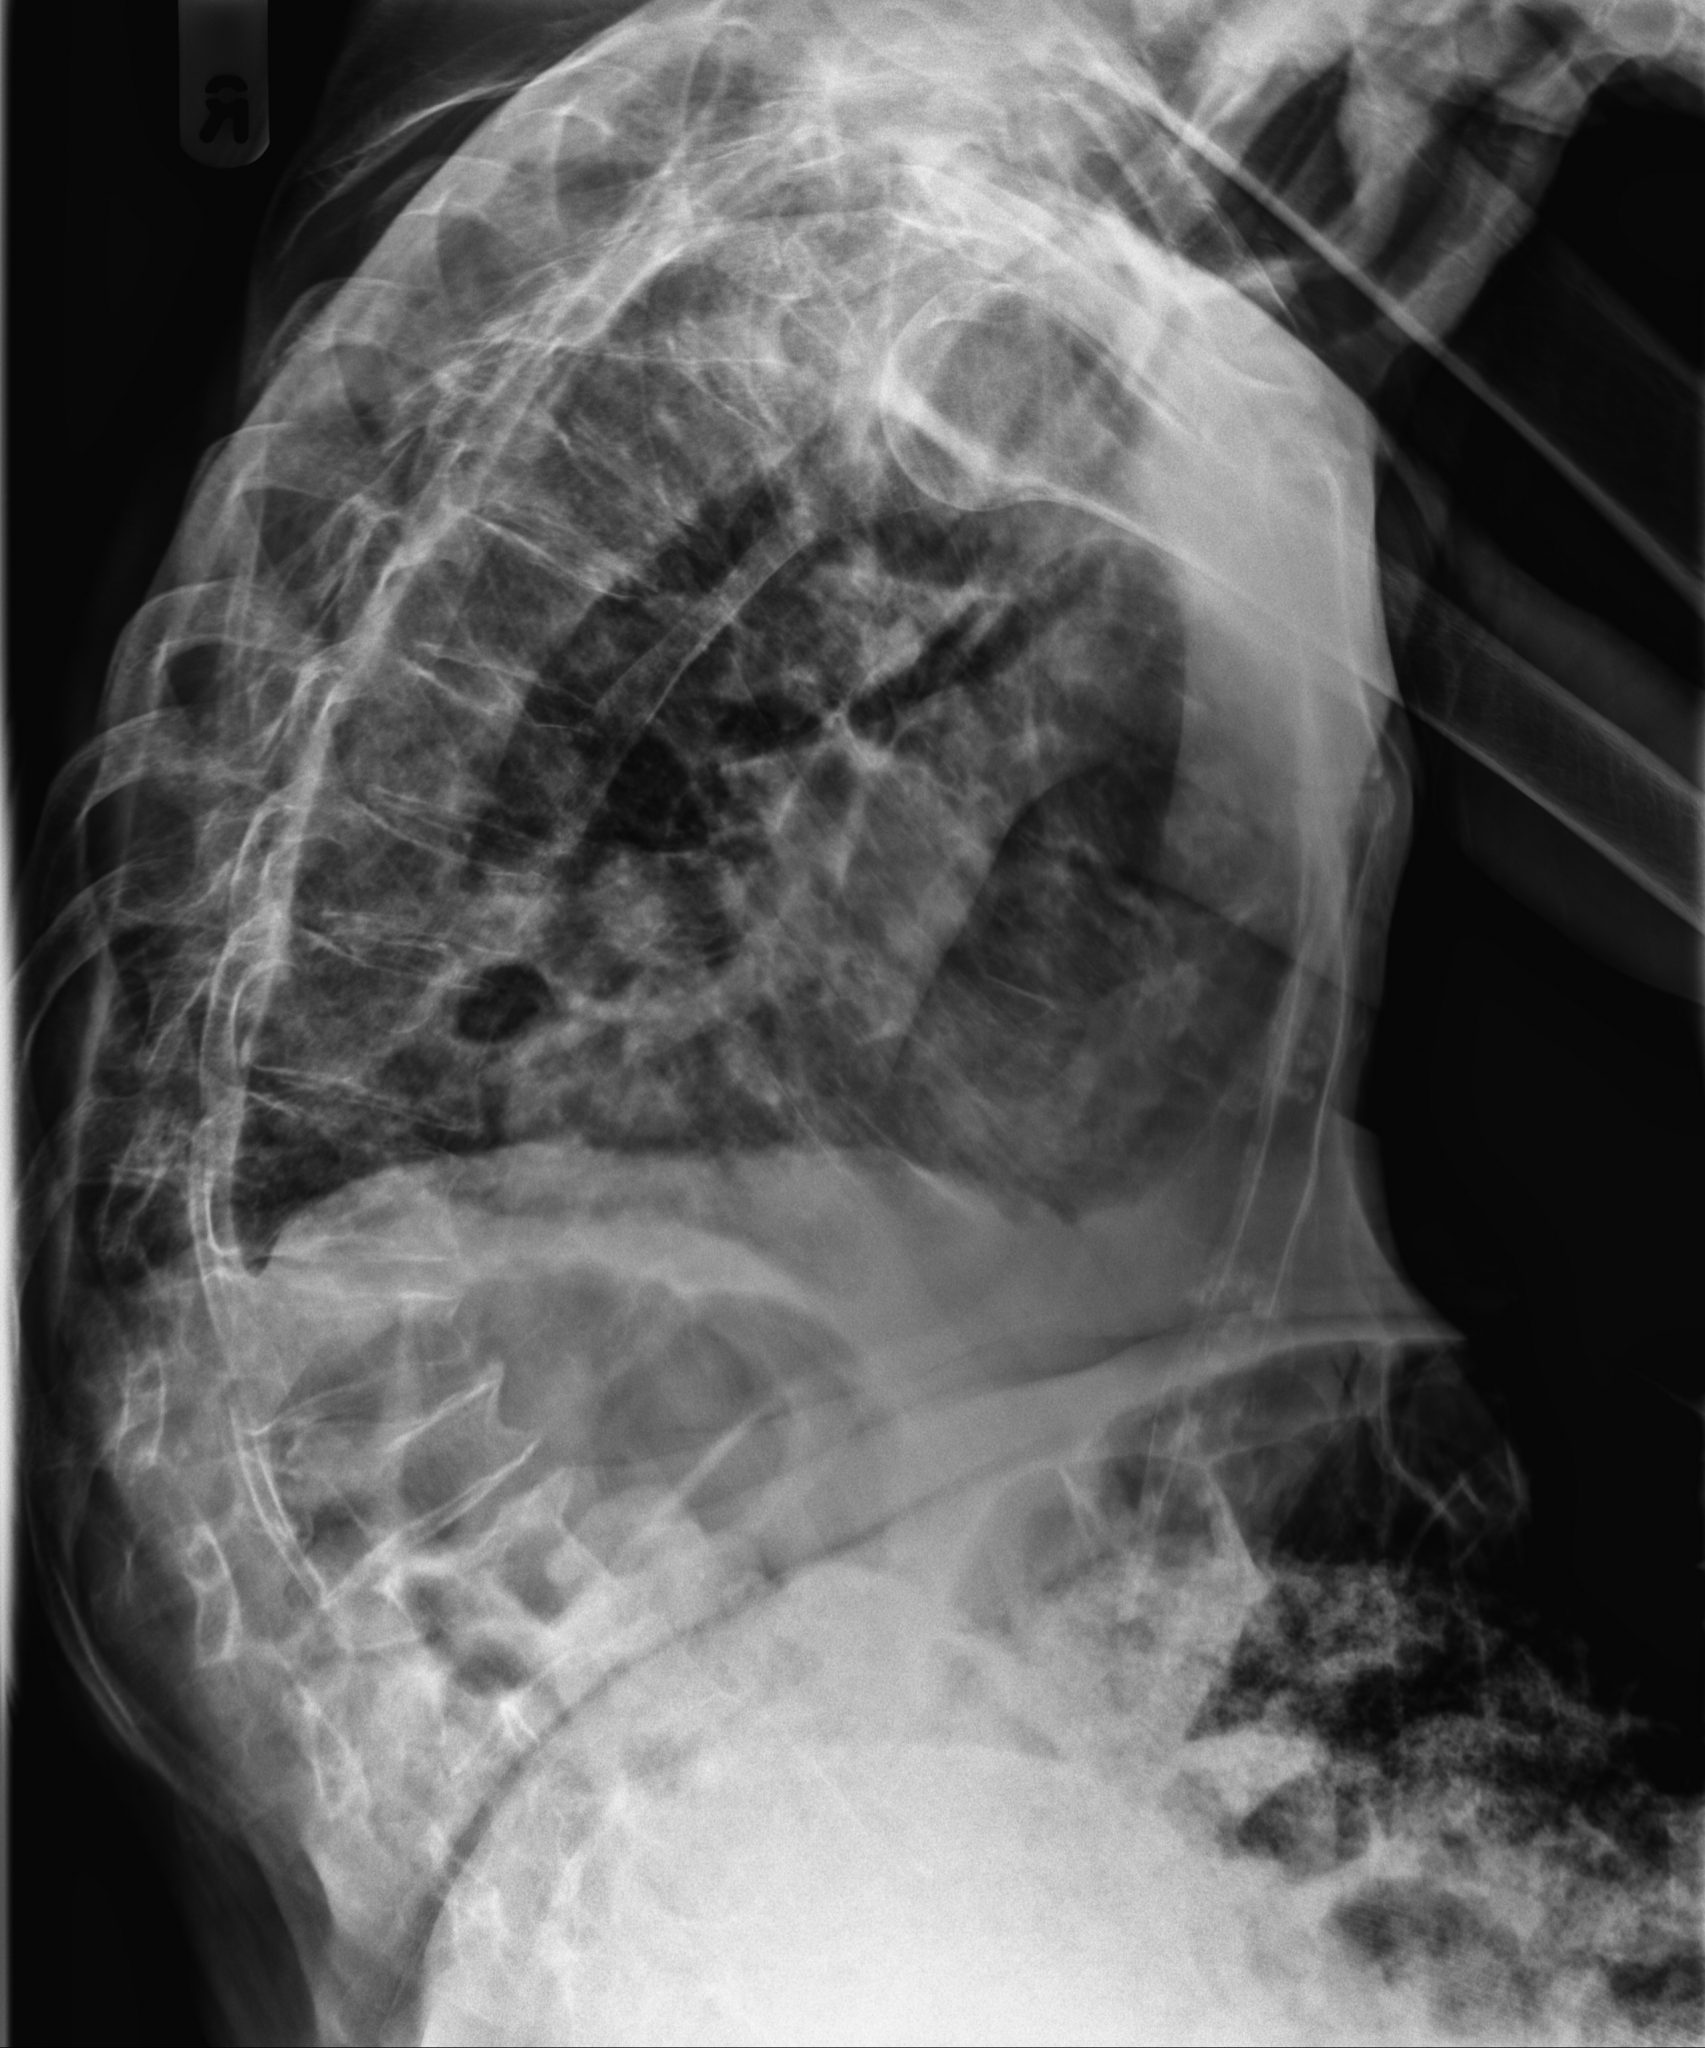

From radiologypics.com

Thoracic Spine Compression Fractures Vertebra Plana Compression Fracture Kyphosis This topic will review the clinical. compression fractures can happen to any part of your spine, but they usually occur in the thoracic spine (middle. thoracolumbar fractures may significantly change the spinal biomechanics. when symptomatic, they cause significant pain and loss of function. osteoporotic vertebral compression fractures are very common fragility fractures of the spine that. Compression Fracture Kyphosis.

Plain radiograph of a patient with an L3 compression fracture with the Compression Fracture Kyphosis patients with multiple compression fractures and progressive loss of vertebral body. vertebral compression fractures (vcfs) are the most common complication of osteoporosis, affecting more than 700,000 americans annually. compression fractures can happen to any part of your spine, but they usually occur in the thoracic spine (middle. The loss of height in the. when symptomatic, they. Compression Fracture Kyphosis.